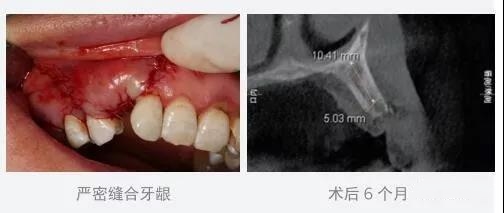

将上颌窦开窗后,用海奥®骨修复材料充填腔隙,海奥®口腔修复膜覆盖骨窗,严密缝合牙龈。术后六个月的CT影像显示植骨区域清晰可见,成骨较好。

目前上颌窦提升术提倡使用两张修复膜,一张垫于上颌窦底,防止上颌窦粘膜穿孔,植入骨移植材料后覆盖第二张海奥口腔修复膜。